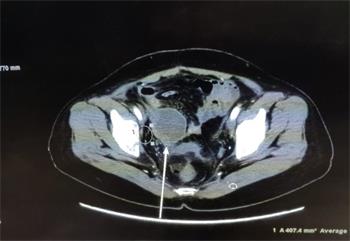

更为惊奇的是,医生在做CT增强扫描时发现肿瘤可能出现大面积的坏死(见图2,箭头所指肿瘤的阴影部份),后来对肿瘤进行了穿刺,病理报告证实了,肿瘤中间部份变成了坏死组织和炎症细胞(见图3),而这个肿瘤的表面仍然是肝癌细胞(后补充免疫组化报告)。

'图2'

图2

这又是一个天大的奇迹。仅仅五天时间,肝转移瘤居然出现中间大面积坏死现象,肿瘤科主任和PET中心主任均表示肝癌在盆腔的转移瘤在未经治疗的情况下从未见过中间坏死的情况。我想应该是大法的威力让肿瘤坏死。后来表姑做了个射频消融处理了表面的癌细胞,一周后基本恢复正常。